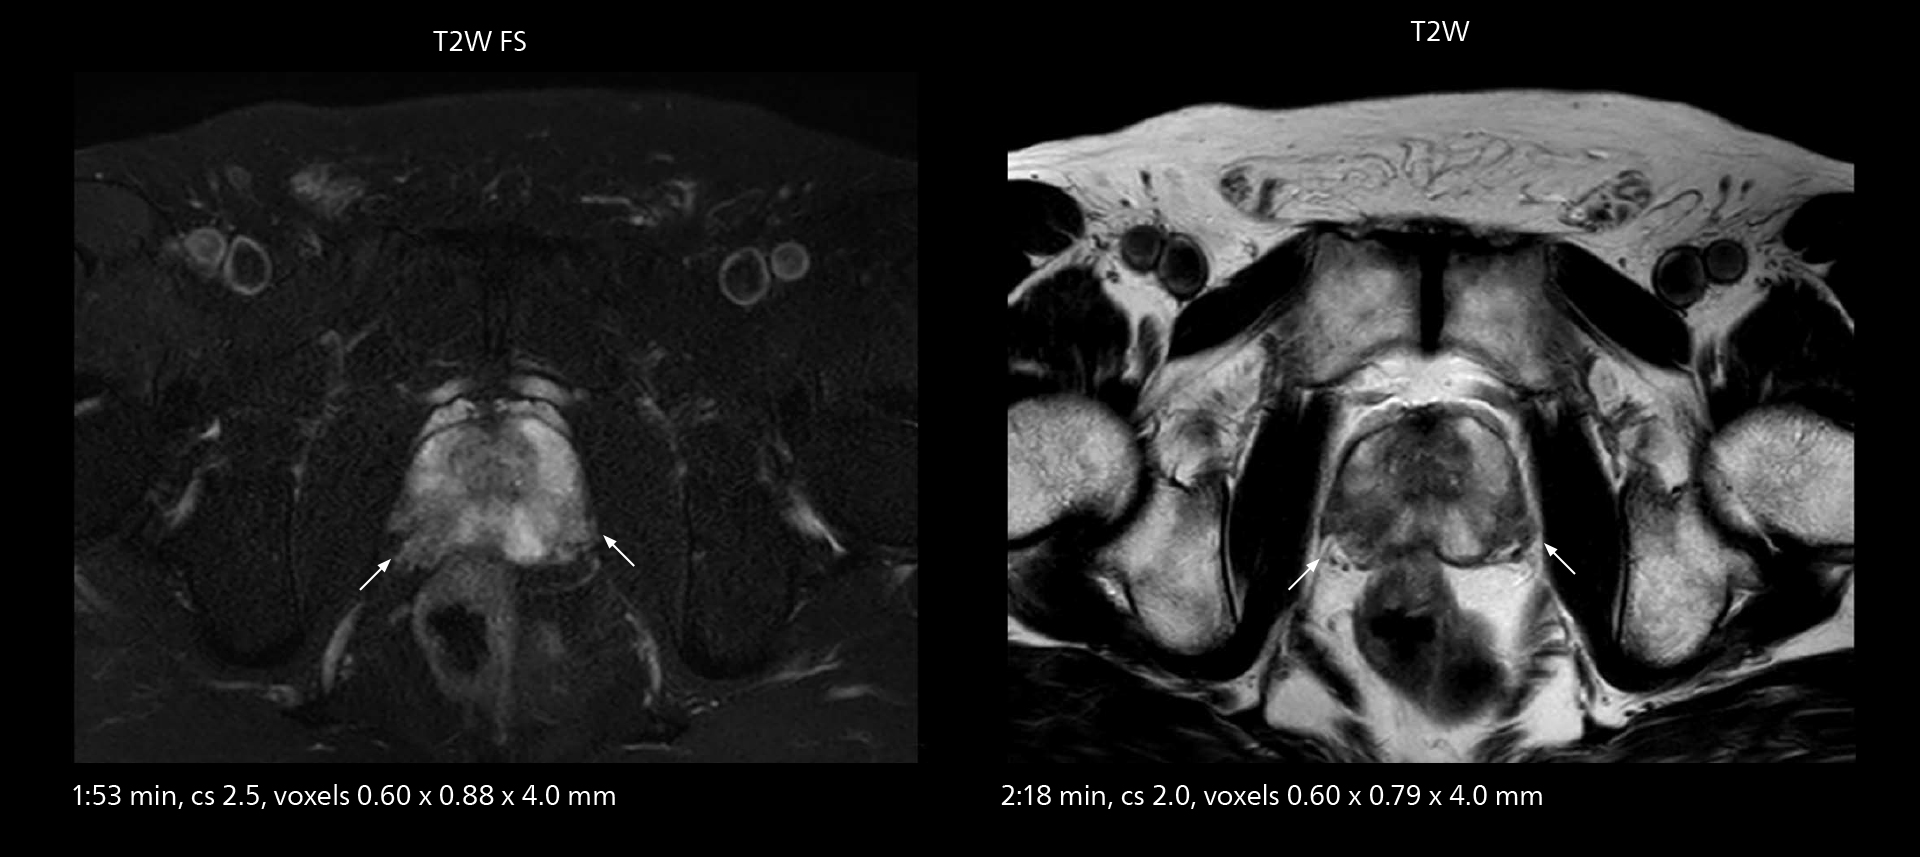

MRI of prostate

Examples of prostate imaging showing faster scan times and improved resolution illustrate the power of SmartPath to Elition X in this case of prostate cancer with PI-RADS score 4.

The high performance of the Vega HP gradients is particularly impressive in DWI. “The Vega HP gradients enable us to scan faster and use b-values as high as 2000, for example in prostate DWI and in DWIBS, which provides image quality that is remarkably improved over the previous system and we are able to more easily see lesions.”